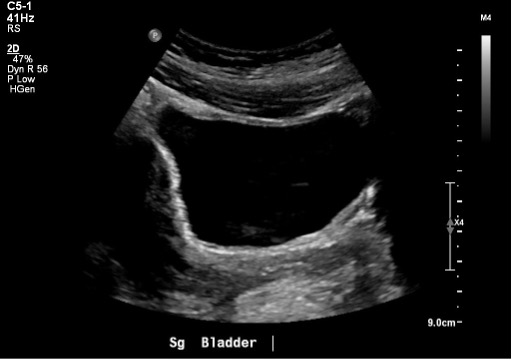

The shape and relationships of the bladder on ultrasound examination will depend on its degree of filling. The sagittal view is triangular (figure 10), and the transverse view is rectangular (figure 11). That said, the shape varies depending on bladder fullness. When distended, the bladder walls appear thinner compared to a thicker appearance when less distended (figure 12).

Figure 11: Normal bladder in the transverse plane

Figure 12: Transverse view of a near empty bladder with thicker walls